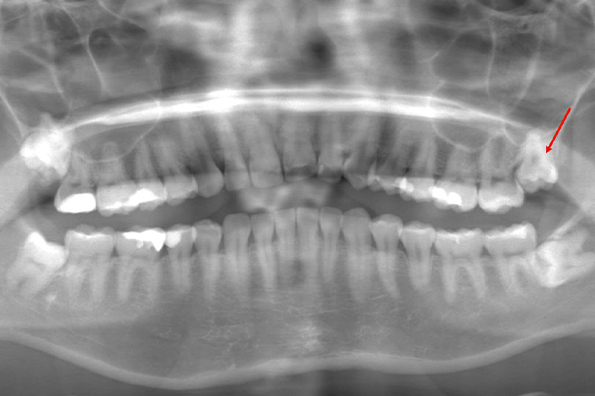

CASE 1

| 年齢・性別 | 30代・女性 |

| 主訴 | 左右に分けて親知らずを抜きたい、できれば痛くなく抜きたい |

| 親知らずのはえ方 | 完全に出ていてまっすぐはえている |

| 抜歯期間 | 15分 |

| 抜歯費用 | 約2,000円(保険内) |

| 抜歯内容 |

何度か虫歯になり痛みはないが早めに抜きたい。 完全に頭が出ているため歯ぐきを切ったり骨を削らずに抜歯しました。 根の形も単純なため抜歯自体は5分もかからず上下ともに終わりました。 術後痛みや腫れも出ていません。 抜歯後は感染をしやすいため必ず抗生物質を飲み切ってください。 |